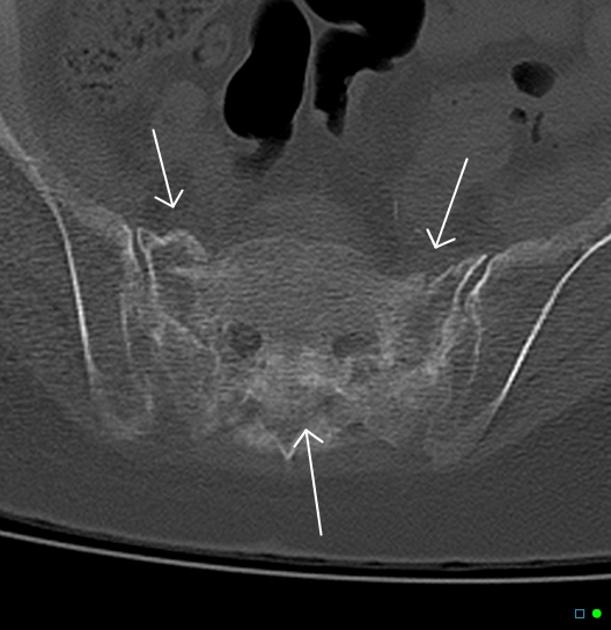

CT影像表现

东风本田征,较为特异性影像表现(冠状位重建)